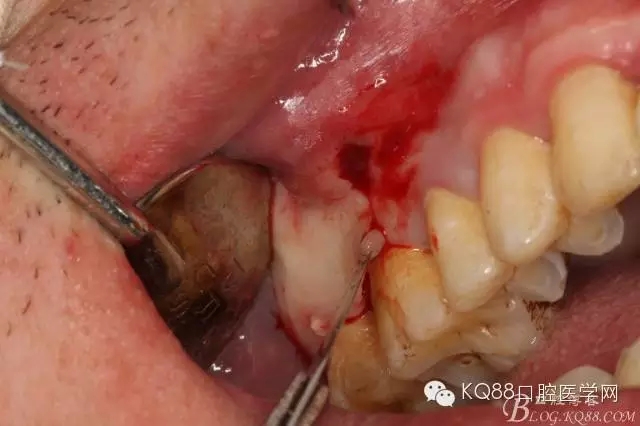

圖6.局部浸潤麻醉下。在16的近中做垂直切口+遠中齦溝內(nèi)及上頜結節(jié)水平切口

圖7.翻全厚瓣。發(fā)現(xiàn)17牙根方的骨質(zhì)破損,破損處有大量膿性血性分泌物溢出。

圖8.繼續(xù)翻瓣至上頜結節(jié)處,發(fā)現(xiàn)骨壁缺損有花生米大小,腔隙內(nèi)有大量肉芽組織。

圖9.清理缺損骨腔內(nèi)的膿性分泌物及炎性肉芽組織,目的是找到18在哪里,隱約可以看到18白色的小樣子喲。

圖10.去除了覆蓋在18牙冠表面的肉芽組織,暴露出18的部分牙冠。

圖11.千辛萬苦,總算看到18的合面了,唯一難做的就是牙齒在里面打轉(zhuǎn)轉(zhuǎn),固定不住牙,也無法夾持住它,好郁悶。

圖12.沒辦法,只能往16旁邊去了點骨質(zhì)。才把18它呼喚出來。病人說他的嘴巴快被拉扯了。

圖13.取出18后,出現(xiàn)的巨大空腔,上頜竇粘膜完全破損。